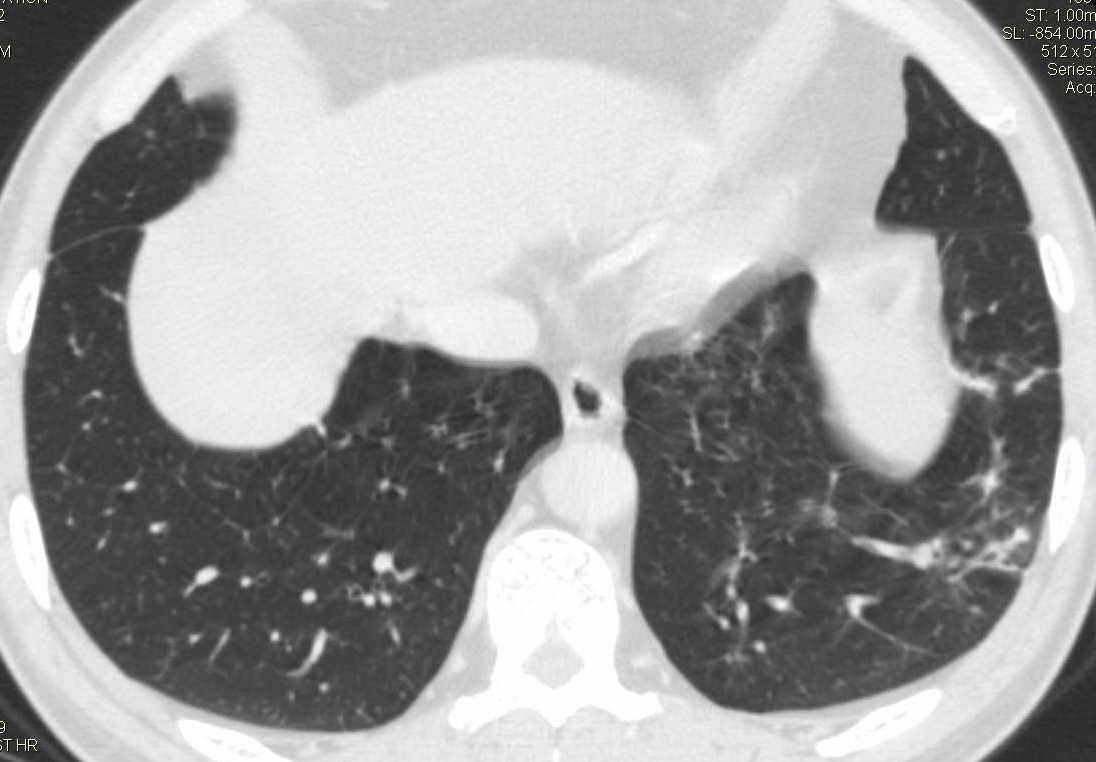

标题: CT15857:男性 58岁 咳痰带血 无发热 请各位大侠发表一下意见 [打印本页]

标题: CT15857:男性 58岁 咳痰带血 无发热 请各位大侠发表一下意见

两肺下叶肺纹理增多、增粗并呈“树芽状”改变。支气管扩张呈囊状,部分呈柱状改变。其周围可见散在的斑片样及条索样密度增高影,右肺下叶近叶间胸膜可见一形态不规则的高密度结节影,并与胸膜粘连。

考虑:支扩并发感染。

双肺多发炎性病灶,结核可能性大,建议抗炎治疗复查.右肺下叶前基底段结节灶,高度警惕肺癌可能

双肺间质性改变(间质纤维化?)伴支扩。右肺下叶有毛刺的小结节,考虑周围型肺癌可能性。